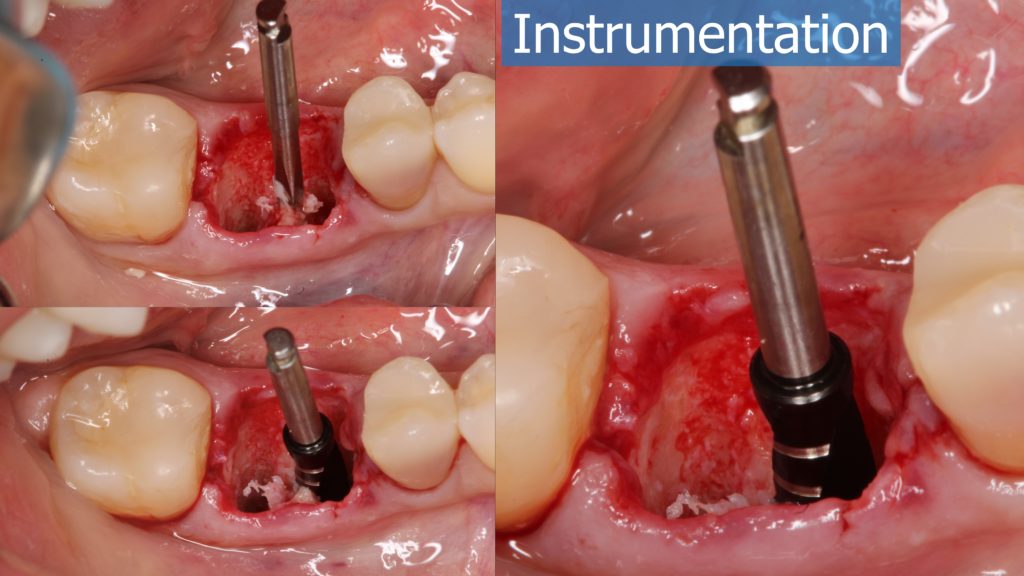

6-12 Months, Augma Bone Cement Academy, Bone Cement Expert, Clinical Cases, Clinical Indication, Clinician, Collagen Sponge/Plug, Coverage Used, Dental Notation, Images, Immediate Placement, Lower Left Molar, Media, Post-Op Period, Socket Grafting, Wound Dressing

Immediate Posterior Implant with Bone Graft

A healthy 36 year old woman comes to the clinic with pain and swelling in the area of the inferior left molars. In the intraoral observation, a vestibular fistula was identified, and the complementary exams confirmed a bone lesion caused by a root perforation (poorly executed false post) on the first lower left molar #36 (19). It was decided to do antibiotic therapy for a week and then the tooth extraction with immediate implant placement and bone graft. 4 months post-op the definitive zirconia/ceramic crown would be was made.